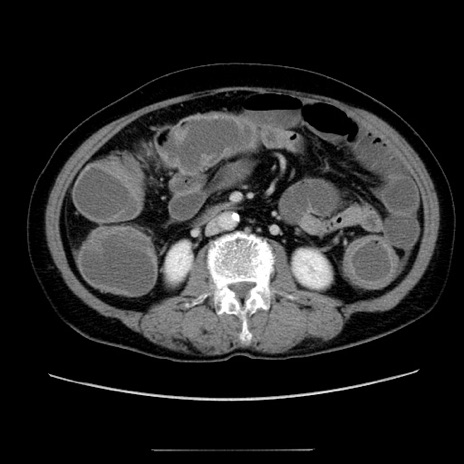

症例5(横断像)

【症例】70歳代女性

【主訴】お腹が張る

【現病歴】1週間くらい前から腹部膨満の自覚あり。昨日夜から増悪したため、本日救急外来受診。

【身体所見】意識清明、BT 36.5℃、BP 165/106mmHg、HR 80bpm、SpO2 98%、腹部:膨満、軟、自発痛・圧痛なし、触診にて不快感あり、腸蠕動音:減弱

【データ】WBC 12600、CRP 1.04